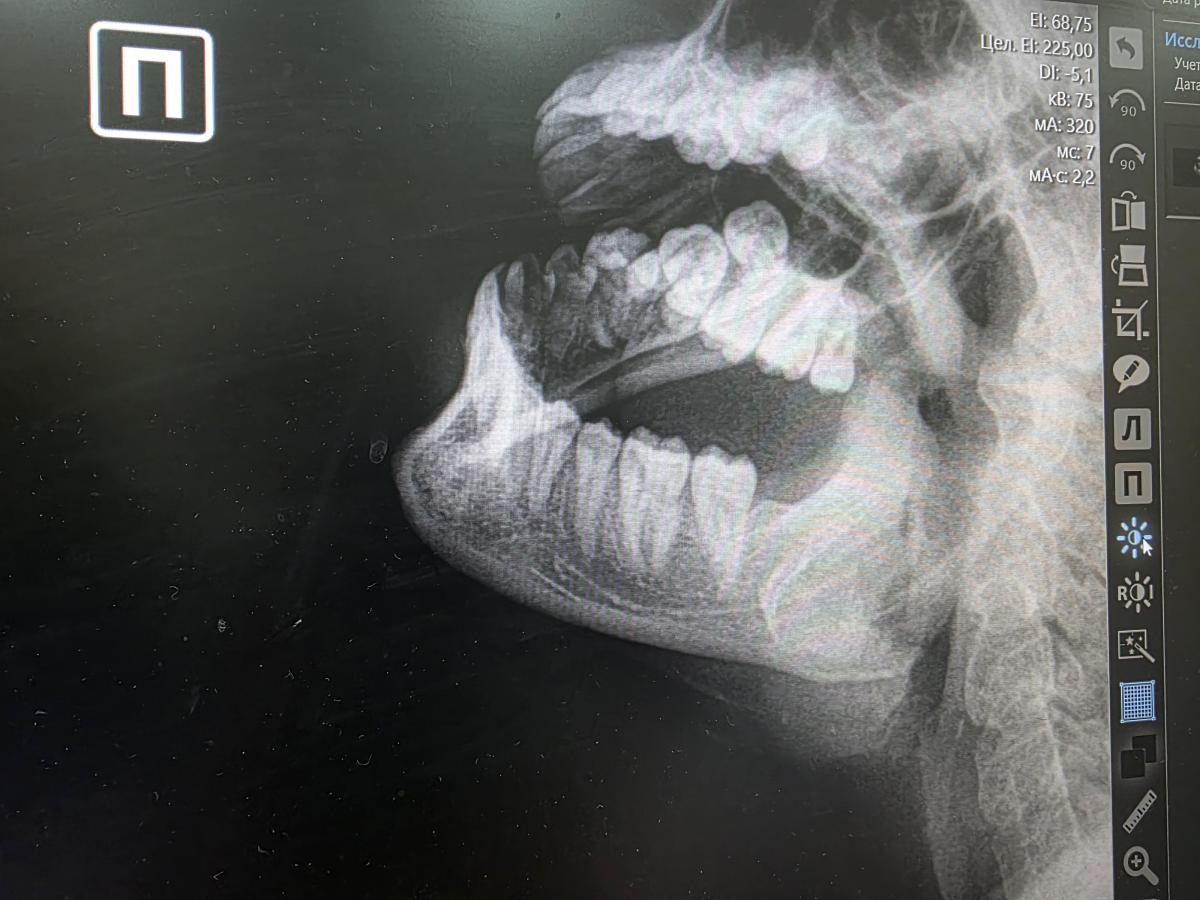

На снимке всё хорошо: шедевральное исполнение не оставляет никаких сомнений!